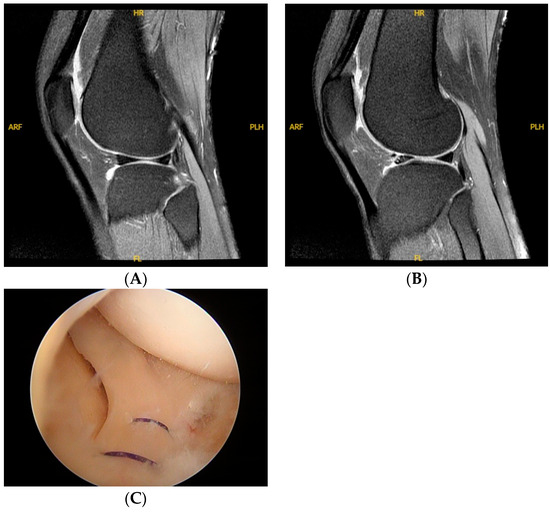

| MRI findings | |

| Suspected lateral anterior horn meniscus tear | 3 (17.6%) |

| Parameniscus tear | 1 (5.9%) |

| Deformed anterior horn | 4 (23.5%) |

| Effusion | 6 (35.3%) |

| Fluid accumulation noted at the anterior horn | 7 (41.2%) |

| Arthroscopic findings | |

| Unstable anterior horn | 17 (100%) |

| Parameniscus tear | 17 (100%) |